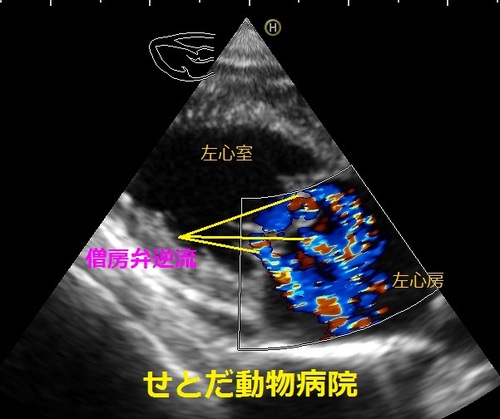

心臓の検査は、「聴診」「心エコー検査」「胸部レントゲン検査」「血液検査」が主体です。心臓の中の構造、特に弁膜の状態を調べるためには「心エコー検査」が特に有効です。

心臓の壁の厚さ、心臓の壁の動き具合、心臓の中の血液の流れ具合などを調べる事ができます。弁膜症の場合は閉鎖不全や血液の流れの悪い部分を探すために役たちます。

写真は小型犬の「僧帽弁閉鎖不全」による「僧帽弁逆流」です。